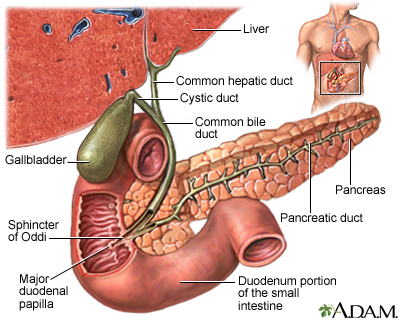

ERCP and a procedure called a sphincterotomy may be done to find or treat gallstones in the common bile duct.

Blockage by gallstones may cause swelling or infection in the:

- Gallbladder (cholecystitis)

- Tube that carries bile from the liver to the gallbladder and intestines (cholangitis)

- Pancreas (pancreatitis)